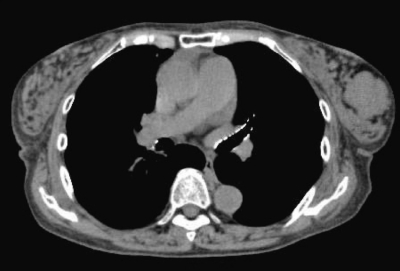

74歳の女性。左乳房のしこりを主訴に来院した。30 年前に左乳房にゴルフボール大のしこりがあるのに気付いていたが、大きさに変化がないためそのままにしていた。先日、入浴時にしこりの増大に気付き心配になり受診した。乳房に色調の変化やひきつれを認めない。表面平滑で弾性硬、可動性良好な径3cmの腫瘤を触知 する。腋窩リンパ節を触知しない。左乳房のマンモグラムと胸部CTとを示す。

考えられる診断はどれか。

e. 乳腺葉状腫瘍